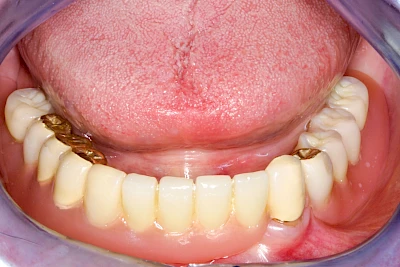

Fehlen einzelne Zähne und die Nachbarzähne sind unbeschadet oder gut zahnärztlich versorgt, werden immer häufiger Implantate gewählt, um die Lücken zu schließen. Auch bei größeren oder verteilten Lücken, wenn keine herausnehmbare Prothese gewünscht ist, werden Implantate für Kronen- bzw. Brückenversorgungen gesetzt. In Einzelfällen entscheiden sich sogar zahnlose Patienten für eine festsitzende Versorgung auf Implantaten.

Varianten zur Verankerung von festsitzendem Zahnersatz auf Implantaten